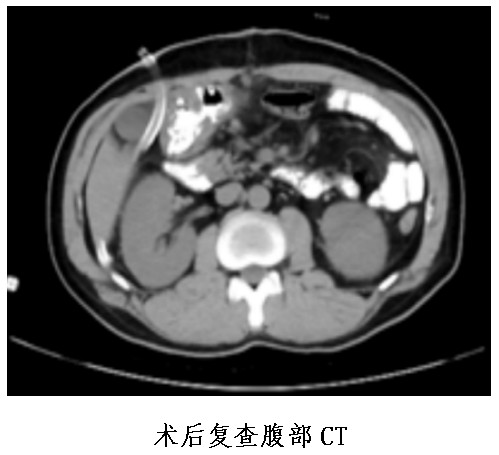

普外中心主任兼胃腸外科主任譚曙光組織醫(yī)師團(tuán)隊(duì)就患者治療方案進(jìn)行討論,認(rèn)為該名胃體神經(jīng)內(nèi)分泌瘤患者,符合手術(shù)指征。經(jīng)過(guò)反復(fù)評(píng)估并與患者本人及家屬溝通,最終譚曙光醫(yī)師團(tuán)隊(duì)決定摒棄傳統(tǒng)的胃切除術(shù),選擇腹腔鏡根治性近端胃切除+D2淋巴結(jié)清掃及雙通道吻合(食道空腸over-Lap吻合及空腸遠(yuǎn)端胃吻合)術(shù),有效減少了反流性食道炎等術(shù)后并發(fā)癥的發(fā)生。1月9日,患者完成了手術(shù),術(shù)后恢復(fù)順利并于22日出院。

據(jù)悉,腹腔鏡根治性近端胃切除+D2淋巴結(jié)清掃及雙通道吻合(食道空腸over-Lap吻合及空腸遠(yuǎn)端胃吻合)術(shù),屬于腹腔鏡下IV級(jí)高難度手術(shù)。該手術(shù)的優(yōu)點(diǎn)為全部操作均在腹腔鏡下完成,對(duì)腹腔干擾少,術(shù)后切口疼痛及腸粘連發(fā)生率明顯減少;能完整切除胃部病灶,最大限度地保留患者的正常胃組織及功能;能大大減少胃切除術(shù)后的嚴(yán)重的胃食管反流性疾病等并發(fā)癥的發(fā)生幾率。